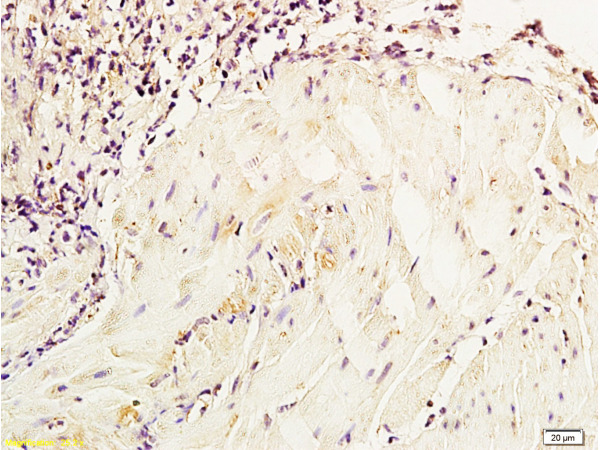

This page contains information on snap canine parvovirus antigen test kit for veterinary use. The most common type urinary bladder cancer seen in cats is rooted from a tumor called transitional cell carcinoma (tcc). The original bladder tumor antigen (bta) test is an agglutination assay that measures the level of a membrane protein that is released into the urine when the cancer invades the bladder wall.

Cancer of the urinary tract in dogs can affect the kidneys, ureters, urinary bladder tcc is a malignant tumor that develops from the transitional epithelial cells that line the bladder. Many veterinary patients have clinical signs that mimic a uti, and there is temporary resolution with this is in contrast to the previously available veterinary bladder tumor antigen test (vbta), which is 85% sensitive for tcc. Tumor antigens are useful in identifying tumor cells and are potential candidates for use in cancer therapy. These look for substances that are released by bladder cancer cells.